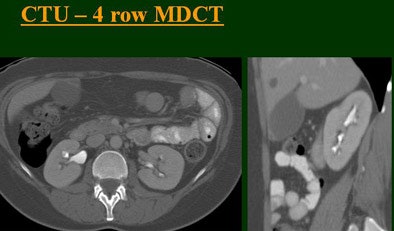

"As we've been scanning through the kidneys, we've been noticing that there has been an increase in the quality images as we go from (single-) to four-, eight-, and 16-row detector scans," Raptopoulos said. "Our purpose, then, was to assess the quality of CTU with progressively improving CT technology from (single-) to 4-, 8-, and 16-row scanners, using a split-injection single scanning technique."

| Top to bottom: Split-bolus CTU improves significantly using a nearly identical protocol but with the addition of more detector rows, from single- (spiral), four-, eight-, and 16-row scanners. All images courtesy of Dr. Vassilios Raptopoulos. |

The single-row scanner required two breath-holds; the other scanners reduced scan time from about 20 seconds (four-slice) down to seven seconds (16-slice). Collimation for the single-row scanner was 5 mm, with 3-mm overlapping reconstructions. Collimation for the four-, eight-, and 16-row scanners was 2.5 mm, 1.5 mm, and 0.5 mm, respectively, with the patients scanned in a prone position.

Based on multiplanar reformatted (MPR) images, there was significant upscale improvement in calyceal detail from the isotropic images provided by single-detector scanning (median score 2) to four- (median score 3), eight- (median score 4), and 16-detector scanning, Raptopoulos said. On MPR images the calyceal were 1, 2, 3, and 5, respectively. The median ureteral filling was 4 for the upper and left-lower ureters, and 3 for the right-lower ureters.